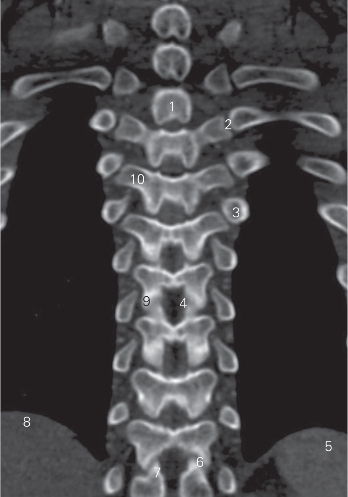

图2-3 经胸椎横突的冠状断层CT图像(骨窗)

1 椎弓板 lamina of vertebral arch 2 肋横突关节 costotransverse joints

3 第5肋肋结节 5th costal tubercle 4 黄韧带 ligamentum flavum

5 脾 spleen 6 关节突关节 zygapophysial joints

7 上关节突 superior articular process 8 肝 liver

9 下关节突 inferior articular process 10 横突 transverse process